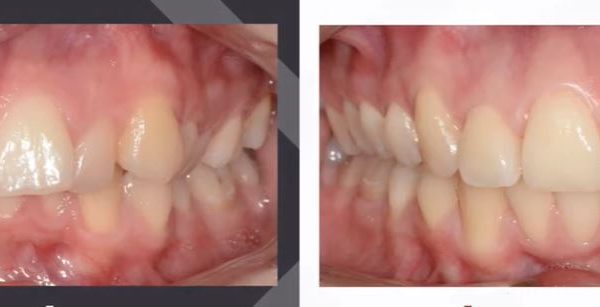

Az elmúlt évekből rengeteg szakmai referenciát tudnánk bemutatni, amelyek különböző fogszabályozási problémákat oldottak meg. Válogatva a több száz esetből, ezen az oldalon olyan képeket, információkat igyekeztünk bemutatni, amelyeknek a segítségével a jövőbeni pácienseinknek azt tudjuk üzenni: A Te fogsorod is lehet gyönyörű!

(Képeket a Pácienseink külön írásos beleegyezésével mutatjuk be!)